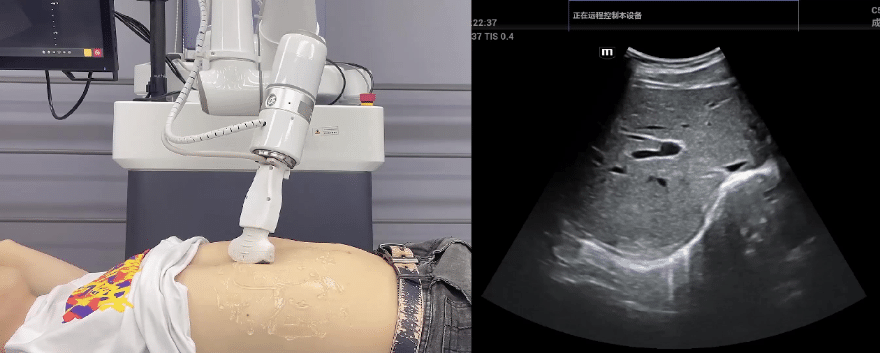

艾利特協(xié)作機(jī)器人搭載庫(kù)柏特自主研發(fā)的機(jī)器人遙操作、多模態(tài)數(shù)據(jù)采集與處理、機(jī)器人模仿學(xué)習(xí)、機(jī)器人力位控制等技術(shù)升級(jí)變革傳統(tǒng)超聲,可實(shí)現(xiàn)遠(yuǎn)程+自主超聲掃查與診斷,從傳統(tǒng)遠(yuǎn)程超聲僅能對(duì)話會(huì)診變革升級(jí)為能對(duì)話、能操作,使得基層患者可就近享受異地三甲專家掃診服務(wù)。實(shí)現(xiàn)專家端與患者端遠(yuǎn)程連接,并支持專家端與多路患者端自由切換控制。

艾利特協(xié)作機(jī)器人與超聲深度打通,最大程度保留醫(yī)生左右手同時(shí)操作傳統(tǒng)超聲的習(xí)慣,并改善其舒適性,超聲檢查實(shí)際應(yīng)用場(chǎng)景展示如下:

肝臟、膽囊、胰腺掃查

腎臟掃查